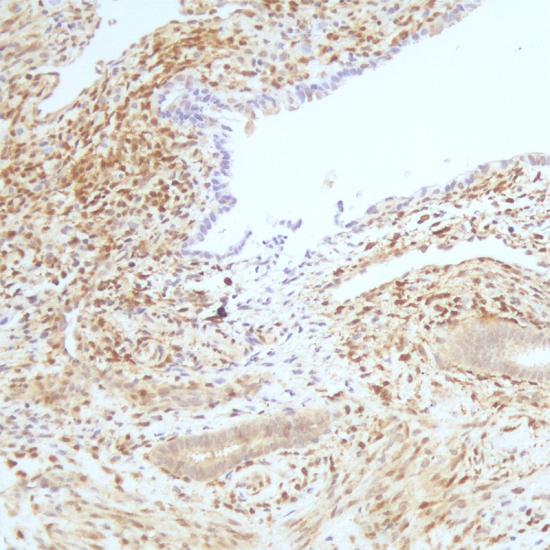

PTEN抗體試劑(免疫組織化學(xué)) 閩廈械備20180201號(hào)

• 陽(yáng)性部位:

細(xì)胞漿/細(xì)胞核

• 陽(yáng)性對(duì)照:

子宮內(nèi)膜癌

PTEN也稱MMAC1或TEP1,是一種腫瘤抑制基因,定位于人染色體10q23。該基因編碼的磷酸酶可調(diào)節(jié)細(xì)胞周期、凋亡的進(jìn)程。研究發(fā)現(xiàn),在人類多種腫瘤和遺傳性腫瘤易感綜合癥疾病中存在 PTEN的缺失和突變,在膠質(zhì)瘤、乳腺癌及前列腺癌中PTEN的表達(dá)與病人預(yù)后有一定相關(guān)性。